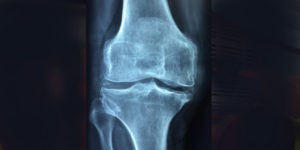

Leczenie kolana skoczka Rzeszów Leczenie bólu kolana, które wynika z przypadłości jaką jest kolano skoczka wymaga podjęcia odpowiednich kroków, rehabilitacji oraz ścisłej współpracy pacjenta, lekarza oraz fizjoterapeuty. Tak zwane kolano skoczka jest specyficzną chorobą ścięgna, która spowodowana jest sumującymi się mikrourazami wynikającymi z przeciążenia rzepki. Należy pamiętać i mieć na uwadze szczególnie to, że choroba […]

Ból stawu fizjoterapia Bóle stawów to bardzo nieprzyjemna dolegliwość, która może pojawić się u osób w różnym wieku i może mieć wiele przyczyn. Bóle stawów mogą pojawić się o każdej porze dnia. Często nawet wstając rano, po długim nocnym wypoczynku, ręce zdają się być bardzo ciężkie, a zejście ze schodów powoduje dyskomfort i ból. To […]